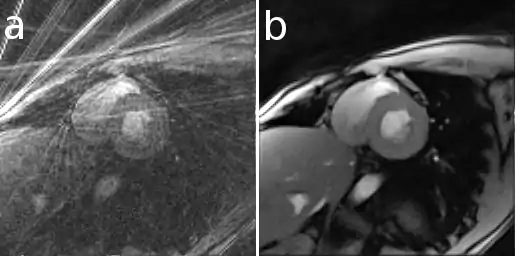

Here is an example that illustrates the benefits of iterative image reconstruction for cardiac MRI.[21]